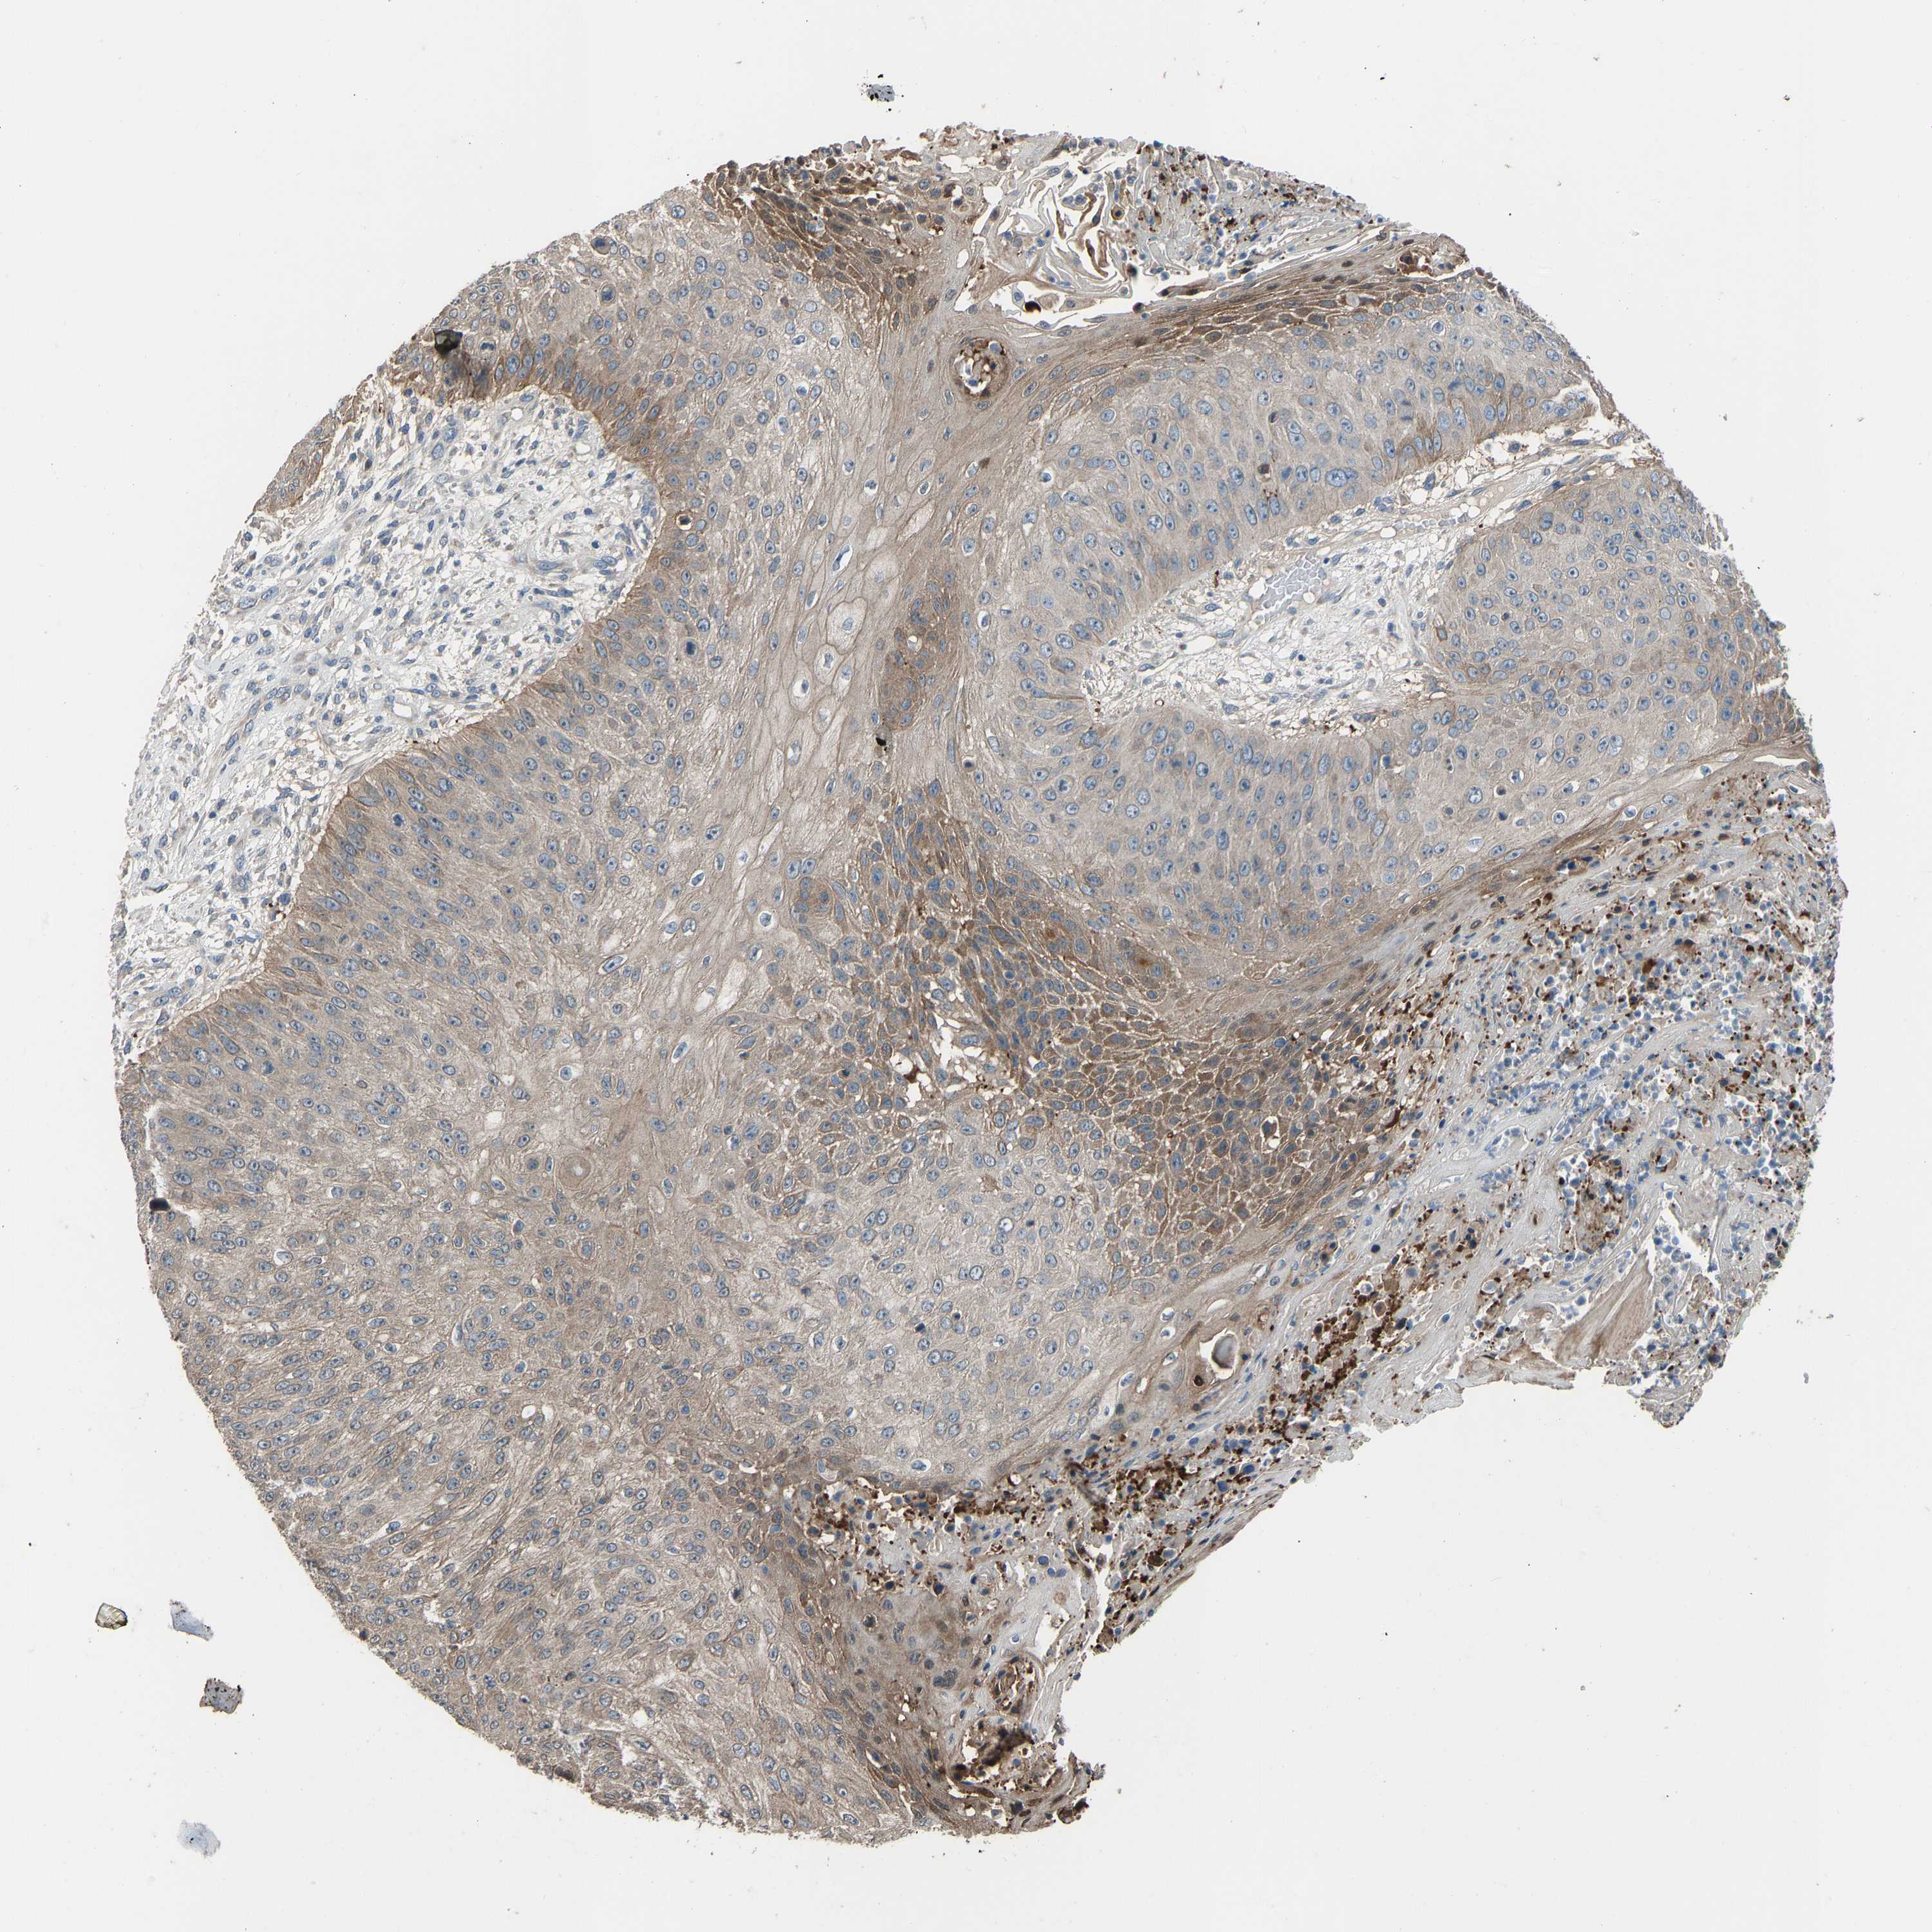

SKIN CANCER - Protein expressioni

A mouse-over function shows sample information and annotation data. Click on an image to view it in a full screen mode. Samples can be filtered based on level of antibody staining by selecting one or several of the following categories: high, medium, low and not detected. The assay and annotation is described here.

Antibody stainingi

Antibody staining in the annotated cell types in the current human tissue is reported as not detected, low, medium, or high, based on conventional immunohistochemistry profiling in selected tissues. This score is based on the combination of the staining intensity and fraction of stained cells.

Each image is clickable and will lead to virtual microscopy that enables deeper exploration of all samples and also displays staining intensity scores, fraction scores and subcellular localization as well as patient and tissue information for each sample.

Antibody CAB018971

Squamous cell carcinoma, NOS

Squamous cell carcinoma, metastatic, NOS